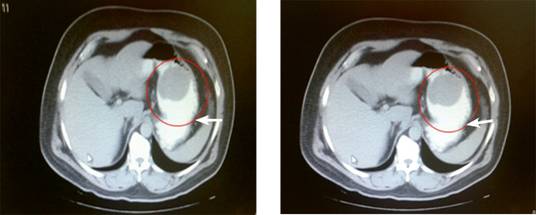

Al día siguiente se llevó a cabo tomografía computada (TC) contrastada en la que se observó una tumoración ulcerada de 5-6 cm de diámetro en el fundus gástrico (Figura 1).

Figura 1: Tomografía computada contrastada que muestra imagen hipodensa circular de bordes bien definidos, de aproximadamente 5-6 cm de diámetro mayor, compatible con masa ocupativa en fundus gástrico con datos de ulceración (flecha blanca).